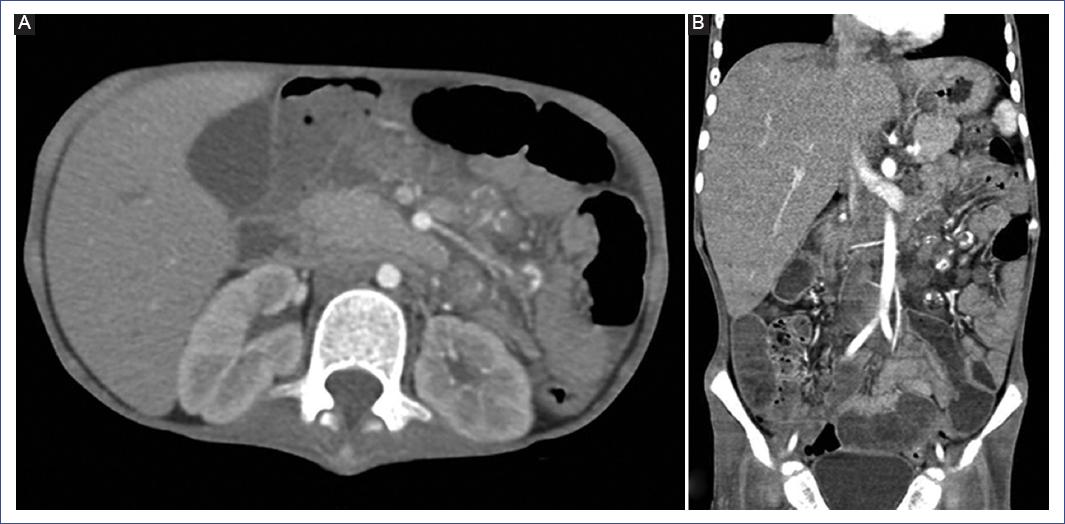

A contrasted abdominal CT scan showed hepatomegaly and multiple mesenteric, para-aortic, and retroperitoneal lymphadenopathies (Figure 2). Due to suspecting a lymphoproliferative picture, a cervical lymph node biopsy was performed on hospital day 3 (HD3).

Figure 2 Contrast-enhanced abdominal CT scan. A: multiple ovoid mesenteric adenopathies. B: hepatomegaly, multiple retroperitoneal adenopathies with a tendency to conglomerate and some with internal calcification images.